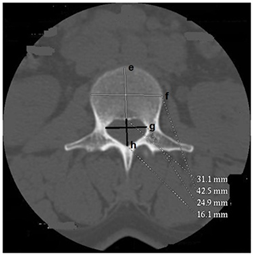

1) The dimensions of the vertebral body (Figure 1 and Figure 2)

The anterior height increased from L1 to L5 and was significantly greater in men than in women (p < 0.001). Posterior height decreased from L1 to L5 and was significantly higher in men than in women (p < 0.001). The transverse and anteroposterior diameters increased significantly from L1 to L5 with mean values significantly lower in women than in men (p <0.001). These different dimensions are shown in Table 1.

Figure 1. Axial section of the L3 lumbar vertebra passing through the pedicles (body and spinal canal dimensions). e: anteroposterior diameter of the vertebral body (DAPCV); f: transverse diameter of the vertebral body (DTCV); g: interpedicular distance of the spinal canal (DIP); h: anteroposterior diameter of the spinal canal (DAPCR).